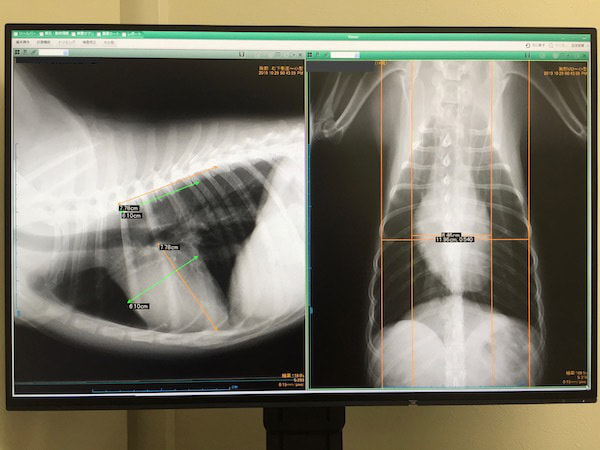

・頭部・胸部・腹部レントゲン検査

<検査結果見本>

・胸部レントゲン検査